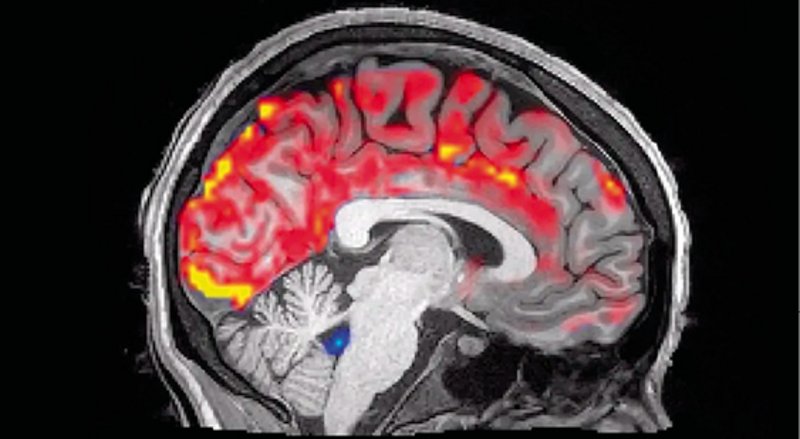

Jeg nævnte tidligere, at hjernen er meget formbar. Det betyder, at områder af hjernebarken kan omfordeles til løsning af andre opgaver ved behov (for eksempel ved genoptræning efter et slagtilfælde), eller at nogle opgaver kan tildeles mere hjerneoverflade, hvis vi øver det intenst (for eksempel fingermotorik ved klaverspil). Dette blev meget tydeligt demonstreret i en række forsøg, hvor normaltseende forsøgspersoner fik bind for øjnene og blev sat til at øve blindskrift. Mens forsøgsdeltagerne øvede sig, målte man på hjernens aktivitet.

I begyndelsen af forsøget var der ingen aktivitet i synsbarken, da bindet for øjnene jo forhindrede synsindtryk. Efter cirka 45 minutter skete der dog noget: Fingerspidsernes berøring af blindskriften begyndte at aktivere synsbarken. Forklaringen er, at den nye opgave (blindskrift) var så krævende, at den ubrugte synsbark blev inddraget til at støtte processen. Dette er smart, for så tildeles der ressourcer, hvor der er behov. Men det er dog meget kortsigtet, for forsøgspersonerne skal jo stadig kunne se efter forsøget.

Så hjernen er plastisk og “smidig”, men forholder sig kun til “nu og her” i sin omfordeling. Dette eksperiment har senere inspireret et forskerhold i USA til at foreslå, at drømme har til formål at beskytte vores synssans, mens vi sover, ved at sørge for periodisk aktivering af den inaktive synsbark. På den måde er synssansen bevaret næste morgen, og vi slipper for at skulle træne synet op på ny hver dag. Det er en spændende teori, som forskerne kalder for “defensiv aktivering”. Teorien passer på mange måder med vores regler for hjernen ovenfor og forklarer også, hvorfor vores drømme primært er visuelle. Teorien er dog vanskelig at underkaste afprøvning i forsøg, men visse læsionsstudier støtter den.